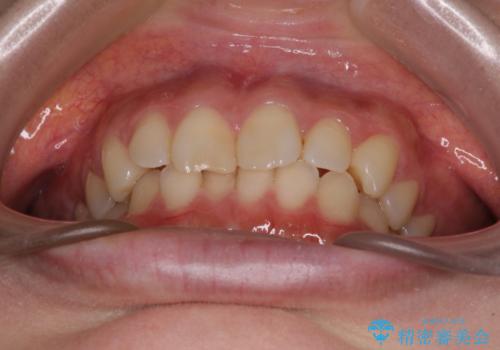

- 近々転勤の予定があるが、早めにインビザラインによる矯正治療を始めたいとのことで来院された患者様です。

上下ともにデコボコの程度は著しいものではなく、インビザラインで十分に対応可能な歯列不正でした。

後戻りによりスペースができてしまうことを避ける目的で、IPR(歯と歯の間を削る)を極力用いない矯正治療を行うこととしました。